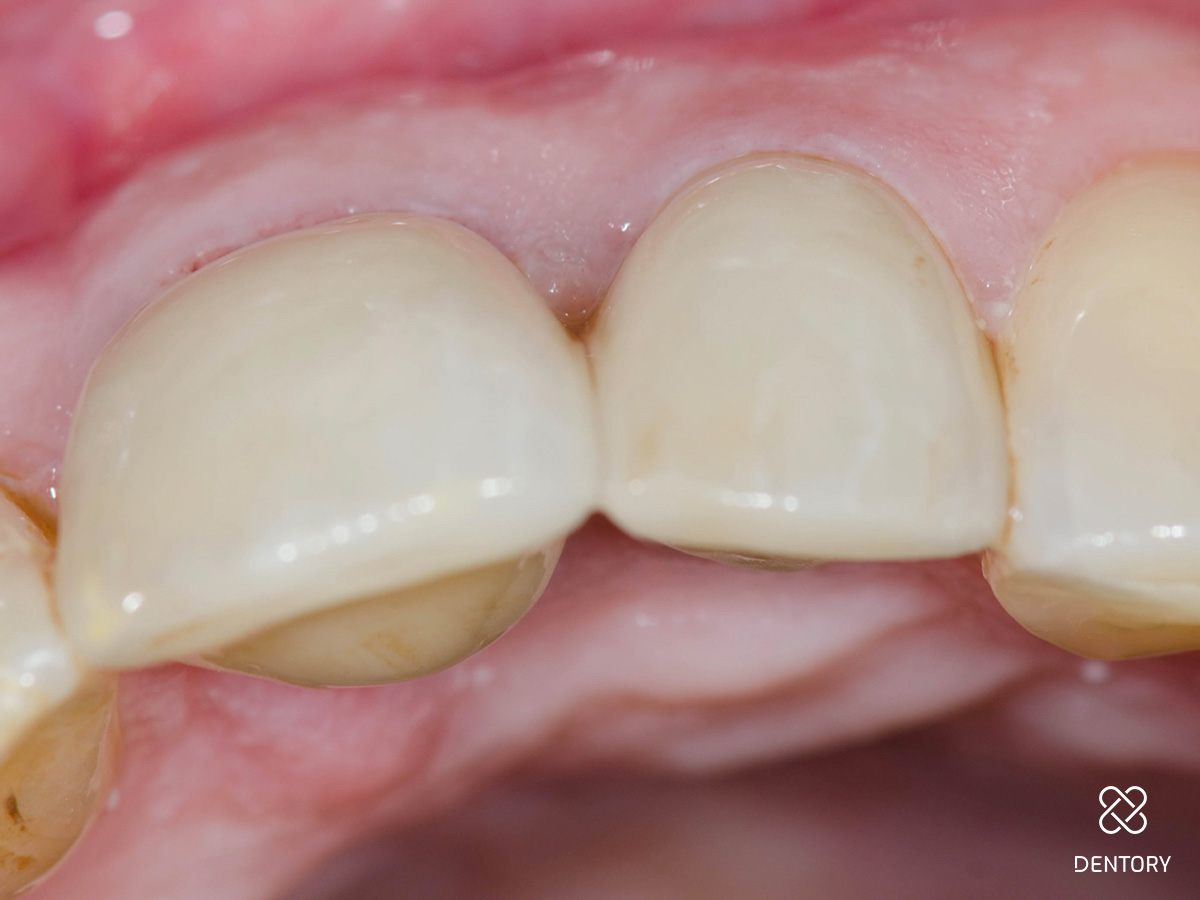

Abbildung 1

Ausgangssituation: Bei einer Routineuntersuchung einer 70-jährigen Patientin...

Abbildung 2

wurden ein ästhetisches Defizit wegen insuffizienter Kronenränder sowie Sekundärkaries an den Zähnen 21 und 22 diagnostiziert.